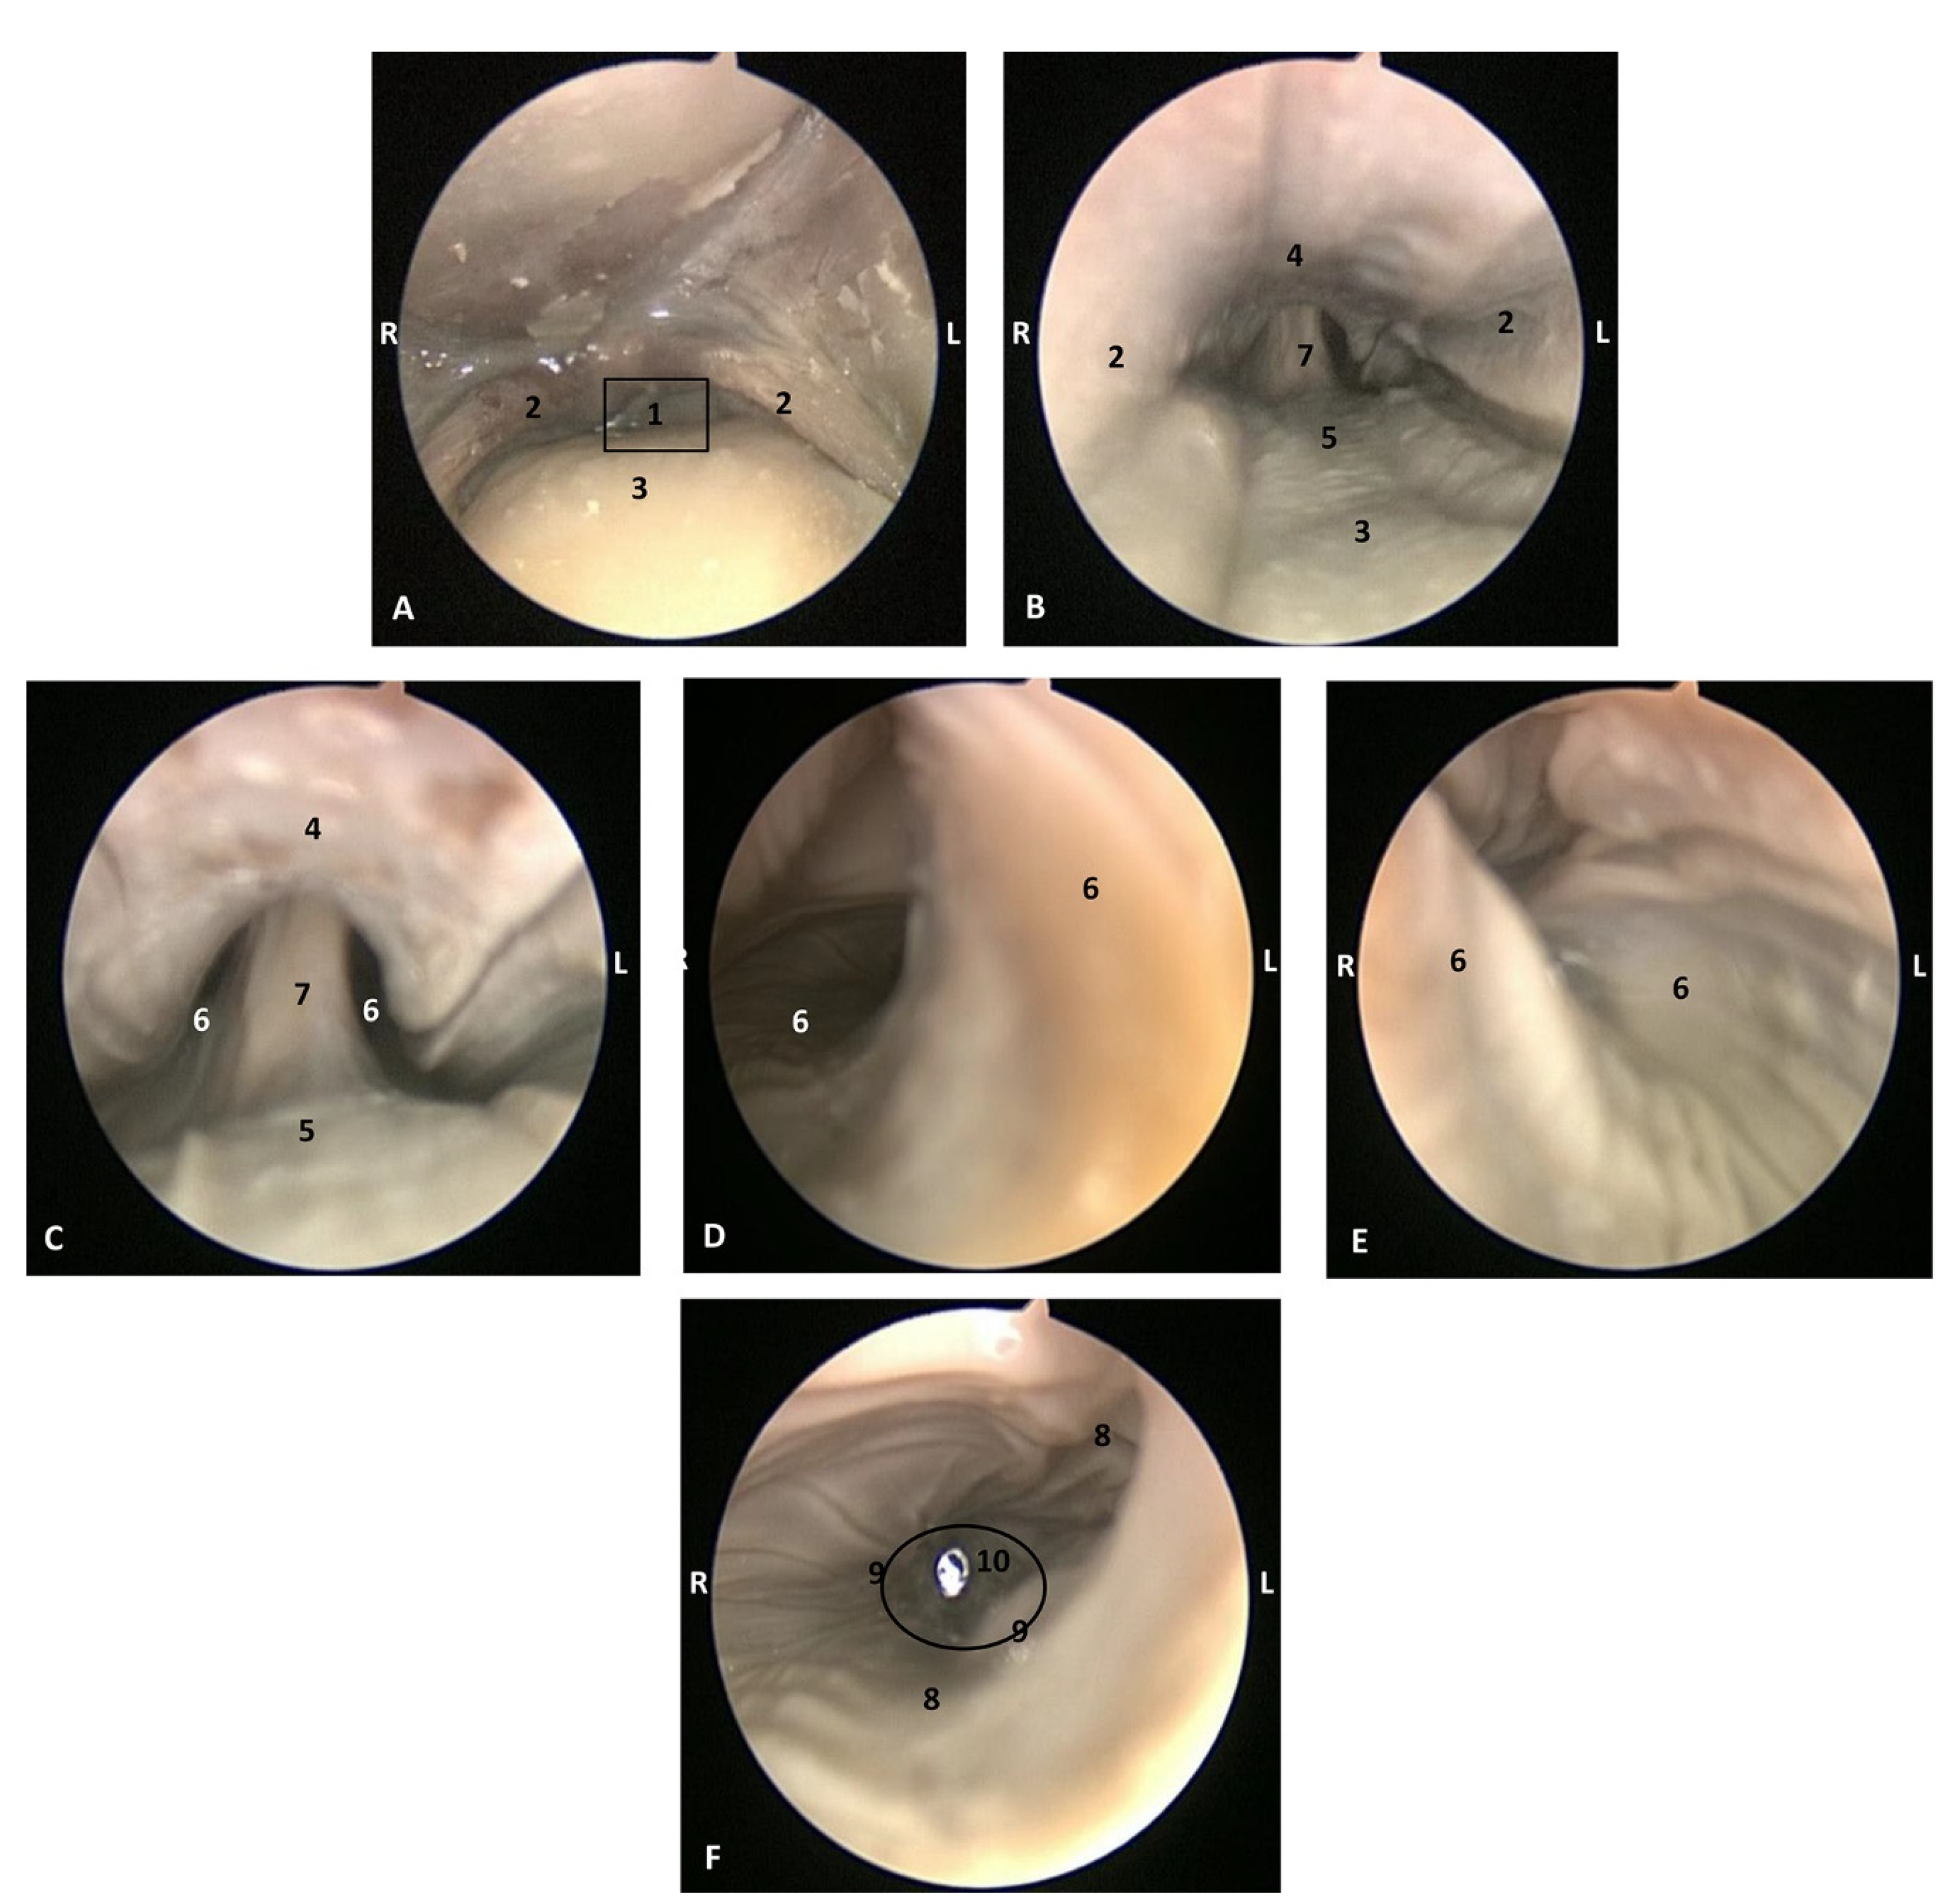

Endoscopic Study

The endoscopic study began at the oropharynx, showed a tightly closed isthmus of the fauces in a young fetus, a Delphinus delphis (dde2). The endoscope could not cross this gate (Figure 16).

Figure 16.

Endoscopic image of the pharyngeal cavity: oropharynx. L (Left) R (Right). Fauces: isthmus. 3.5 months, dde2. 1, Hard palate; 2, Isthmus of the fauces; 3, Arcus palatoglossus or palatoglossus folds; 4, Soft palate; 5, Tongue: root.

The endoscope was passed into the fauces in an older fetus, a Delphinus delphis (dde3) showing a bright mucosa. No lymphoreticular tissue in the floor (tongue), walls (palatoglossus archs or folds) or roof (soft palate) of the fauces was observed. The soft palate is inserted into the ventral crest formed between the lateral and medial lamina of the pterygoid bones. The palatoglossal archs or folds connect to the soft palate through the tongue root. At the end of fauces a soft vallecula continues dorsally with the lingual aspect of the mucosa of epiglottic cartilage. At this level we dorsally observed the intrapharyngeal orifice to allow entry of the larynx into the nasopharynx. Additionally, the laryngopharynx begins with a piriform recess on either side of the larynx cartilages. The left piriform recess is wider than the right one. The dilated oesophageal vestibule is caudal to the recesses whose mucosa is arranged in longitudinal folds changing to small quadrangular folds where the oesophageal mucosa begins (Figure 17).

Figure 17.

Endoscopic image of the pharyngeal cavity. L (Left) R (Right). (A–C) Oropharynx, (A) Fauces. (B–D) Laryngopharynx. 4 months, dde3. 1, Arcus palatoglossus or palatoglossus folds; 2, Soft palate; 3, Tongue: root; 4, Epiglottic vallecula; 5, Epiglottis: lingual surface (mucosa); 6, Piriform recess; 7, Intrapharyngeal orifice (nasopharynx); 8, Oesophageal vestibule; 9, Pharyngoesophageal limit; 10, Oesophageal mucosa.

Both the Stenella coeruleoalba (scop1) and Globicephala melas (gma1) fetuses had a well-developed mucosa at the isthmus and only a narrow passage to the fauces which had a pale lingual mucosa and a grey/brown colour in its walls and roof (Figure 18 and Figure 19).

Figure 18.

Endoscopic image of the pharyngeal cavity: oropharynx. The arrows show where is the tip of the mouth. L (Left) R (Right). (A) Fauces: isthmus. (B) Fauces: inside. 4.5 months, scop1. 1, Hard palate; 2, Isthmus of the fauces (closed); 3, Arcus palatoglossus or palatoglossus folds; 4, Soft palate; 5, Tongue: root.

Figure 19.

Endoscopic image of the pharyngeal cavity: oropharynx. The arrows show where is the tip of the mouth. L (Left) R (Right). (A) Fauces: isthmus. (B) Fauces: inside. 5 months, gma1. 1, Hard palate; 2, Isthmus of the fauces (closed); 3, Arcus palatoglossus or palatoglossus folds; 4, Soft palate; 5, Tongue: root.

A well-defined fauces was observed in an older Delphinus delphis (dde8) and also a broad left piriform recess, with longitudinal folds finishing at the oesophageal vestibule (Figure 20).

Figure 20.

Endoscopic images of the pharyngeal cavity. L (Left) R (Right). (A–C) oropharynx. (B) Fauces. (C–F) Laryngopharynx. 6 months, dde8. 1, Isthmus of the fauces; 2, Arcus palatoglossus; 3, Tongue: root; 4, Soft palate; 5, Epiglottic vallecula; 6, Piriform recess; 7, Epiglottis: mucosa. 8, Oesophageal vestibule; 9, Pharyngoesophageal limit; 10, Oesophageal mucosa.

In this well-developed fetus (Delphinus delphis) (dde9), the endoscope could pass into the choanae to see the nasopharynx and the pharyngeal orifice of the auditory tube; alsothe longitudinal folds changing to small quadrangular folds where the oesophageal mucosa begins (Figure 21). The oropharyngeal mucosa is thickening, the longitudinal folds in the piriform recesses of the laryngopharynx are thin, and a clear difference between the mucosa of the oesophageal vestibule and oesophagus was seen.

Figure 21.

Endoscopic images of the pharyngeal cavity. L (Left) R (Right). (A,B) oropharynx: fauces. (B–F) Laryngopharynx. (G) Left nasopharynx. 7 months, dde9. 1, Arcus palatoglossus; 2, Tongue: root; 3, Soft palate; 4, Piriform recesses (laryngopharynx); 5, Epiglottis: mucosa. 6, Intrapharyngeal orifice (entrance to nasopharynx); 7, Oesophageal vestibule; 8, Pharyngoesophageal limit; 9, Oesophageal mucosa; 10, Pharyngeal orifice of the auditory tube; 11, Choanae; 12, Nasopharyngeal mucosa: longitudinal or striated folds; 13, Nasal septum: vomer bone.

The mucosa of the fauces continues to thicken and has a bright aspect in a Delphinus delphis fetus (dde11). Additionally, in the nasopharynx, the mucosa shows longitudinal folds and small openings surrounding the pharyngeal orifice of the auditory tube (Figure 22).

Figure 22.

Endoscopic images of the pharyngeal cavity. L (Left) R (Right). (A) Oropharynx: fauces. (B) Left nasopharynx. (C) Right nasopharynx. 8 months, dde11. 1, Arcus palatoglossus or palatopharyngeal folds; 2, Tongue: root; 3, Soft palate; 4, Pharyngeal orifice of the auditory tube; 5, Nasal septum: vomer bone; 6, Nasopharyngeal mucosa: longitudinal or striated folds and small openings.

In a juvenile dolphin, we could observe the pinkish mucosa of the nasopharynx with longitudinal folds, but the small holes had less border definition (Figure 23).

Figure 23.

Endoscopic images of the pharyngeal cavity. L (Left) R (Right). (A,B) Left nasopharynx. (C,D) Right nasopharynx. Juvenile, scomu4. 1, Pharyngeal orifice of the auditory tube; 2, Nasal septum: vomer bone; 3, Nasopharyngeal mucosa: longitudinal or striated folds with small holes.